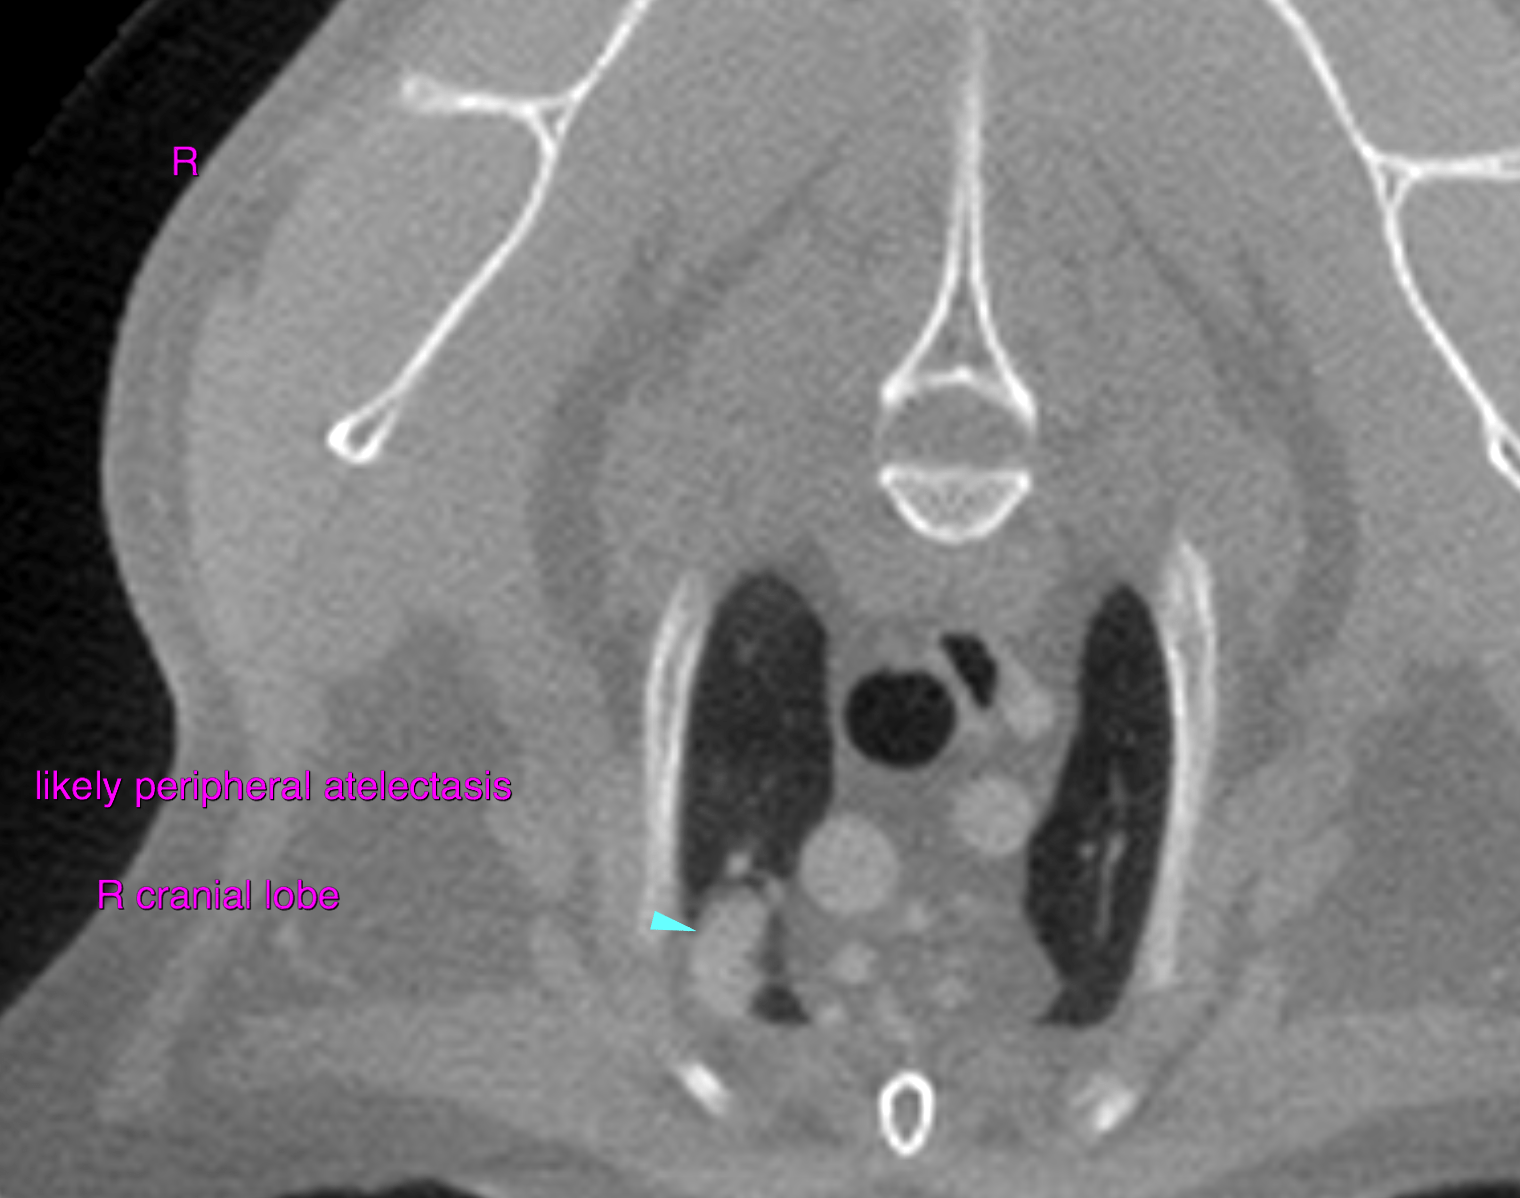

This 10 year old MN DDSH cat has a history of OS exophthalmia, elevated nictitans, mild conjunctival hyperemia/thickening, limited ability to retropulse the globe.

Physical Exam: suspect retrobulbar mass

Reason for Ultrasound Exam: further evaluation prior to possible surgery and staging- patient was taken to surgery by boarded ophthalmologist after CT scan for enucleation and tumor resection.